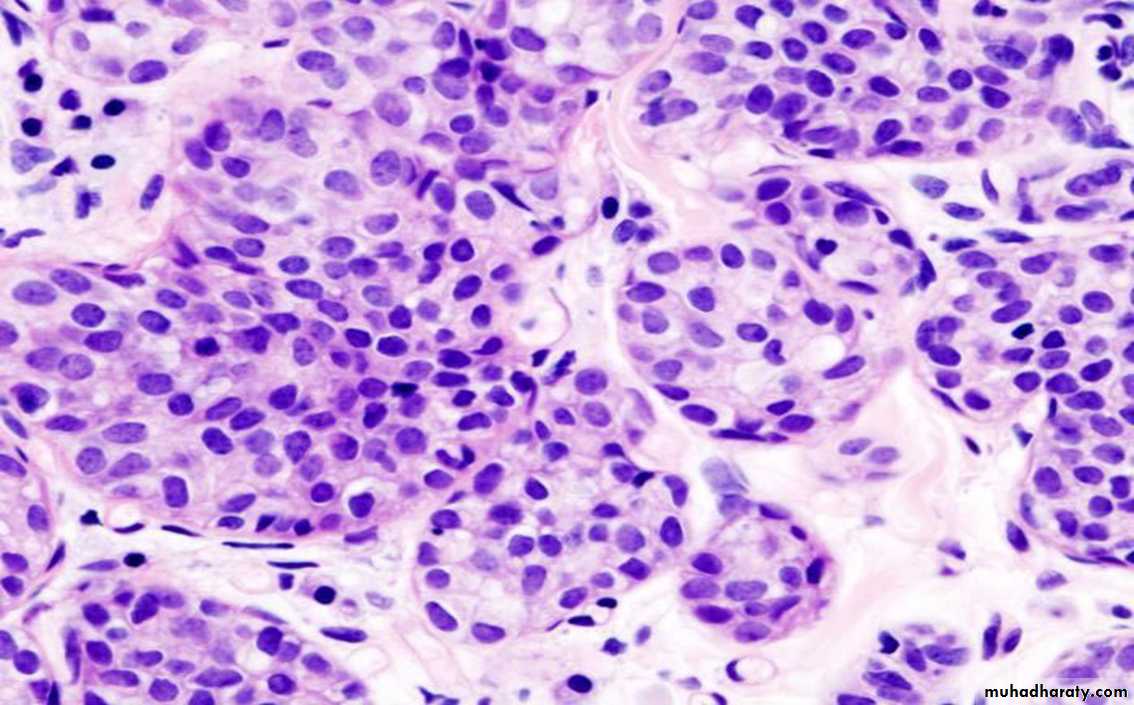

Medullary carcinoma

Invasive Carcinoma

Almost always presents as a palpable mass• Invasive duct carcinoma